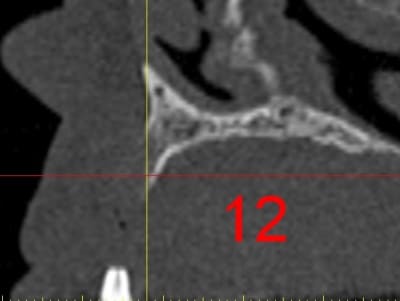

dar12_fcbpom.jpg

La première diapo est un essai pour justifier le concept (os non destiné à une utilisation greffe)

la deuxième est "tapée" dans une tête de femur de mauvais qualité (rejetée)

la troisième et suivante ce sont "les greffons" définitifs.

Pour la mise en forme de la pièce 1 (appui 12) avec la mise en place, le choix de la tête de fémur, et les discussions pour expliquer la mise en forme, il a fallu 1 h environ, qui pourrait etre réduite à une trentaine de minutes, dans un cas comme celui ci, ce qui est déjà énorme pour l'os d'un patient (mise à nu ect...), sans parler des différents stress.